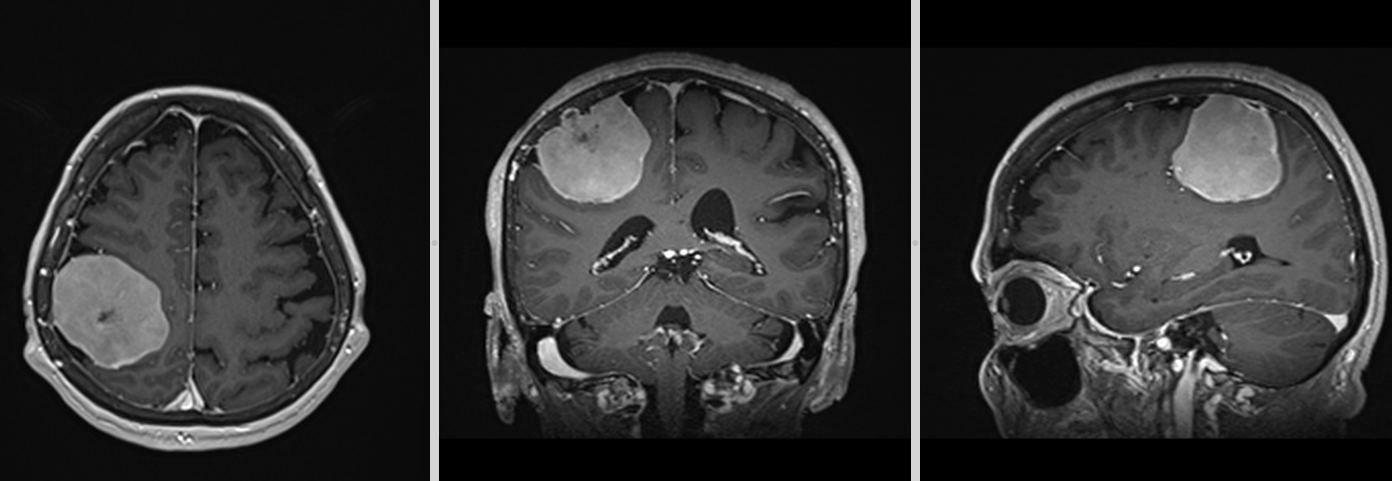

Meningiom olfactiv – RMN preoperator

- RMN – cea mai completă investigație, oferă detalii despre relația cu țesutul cerebral, vasele de sânge și nervii Captarea substanței de contrast este deosebit de importantă.